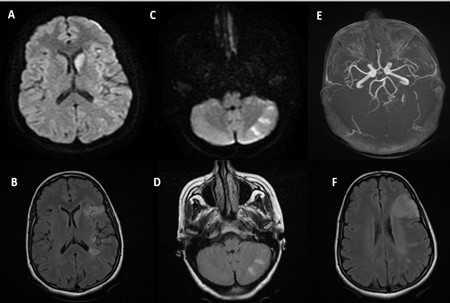

A 44-year-old woman, with a history of miscarriage in 2019 and uninvestigated uterine bleeding since october 2022. She was admitted on December 2022, due to left hemiplegia with facial palsy and language disturbances. These symptoms were preceded by behavioral changes, characterized by agitation and incoherent speech, developing progressively over the preceding month. Physical exam revealed confusion and left hemiplegia. Brain MRI revealed multiple bilateral ischemic strokes involving carotid and vertebrobasilar territories (Figure 1). Due to clinical worsening on the second day of hospitalization, a cerebral CT scan showed a new ischemic stroke of the right middle cerebral artery (Figure 2).

Figure 1: Brain MRI showing multiple ischemic strokes in different territories (A, B, C, D, F) with normal arterial MR angiography (E).